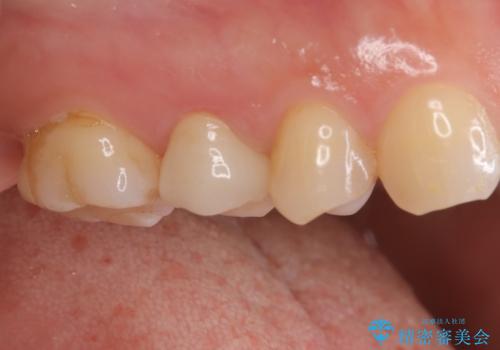

【オールセラミッククラウン】根管治療も行いたい。

- 右上の歯が、噛むと痛いことを主訴に来院されました。

ラバーダムと顕微鏡を用いた根管治療を希望され、治療後は痛みも改善することができました。

その後、オールセラミッククラウンにて修復を行っています。